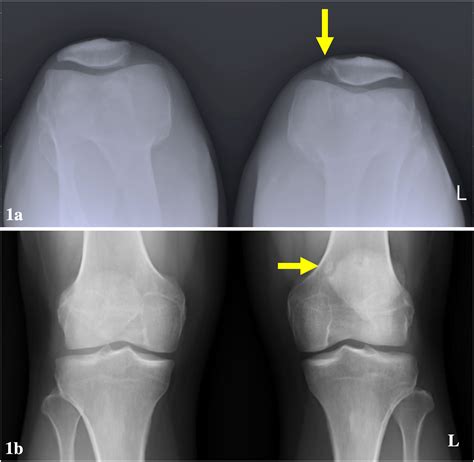

During the typical development of a human skeleton, the patella begins as multiple centers of ossification (bone formation). Usually, these centers fuse together during early adolescence to form one solid, singular bone. In individuals with a Bi Part Patella, this fusion process fails to occur completely, leaving a small accessory bone—most commonly located at the upper outer corner of the kneecap—separated from the main body of the patella.

For many people, this condition is entirely asymptomatic. They may go their entire lives without ever knowing they have a bipartite patella until an X-ray for an unrelated knee issue reveals the anatomical variation. However, for some, the fibrous connection between the main patella and the accessory fragment can become irritated, inflamed, or injured, leading to pain and functional limitations.

⚠️ Note: It is critical to differentiate between a symptomatic bipartite patella and a recent patellar fracture. Unlike a fracture caused by sudden trauma, a bipartite patella typically features smooth, rounded edges on the separated bone fragments, which can be clearly visualized on X-rays.

Diagnosis usually begins with a thorough physical examination, during which a healthcare professional will press on the kneecap to locate the exact point of tenderness. To confirm the diagnosis and rule out other potential causes of knee pain, imaging studies are essential: